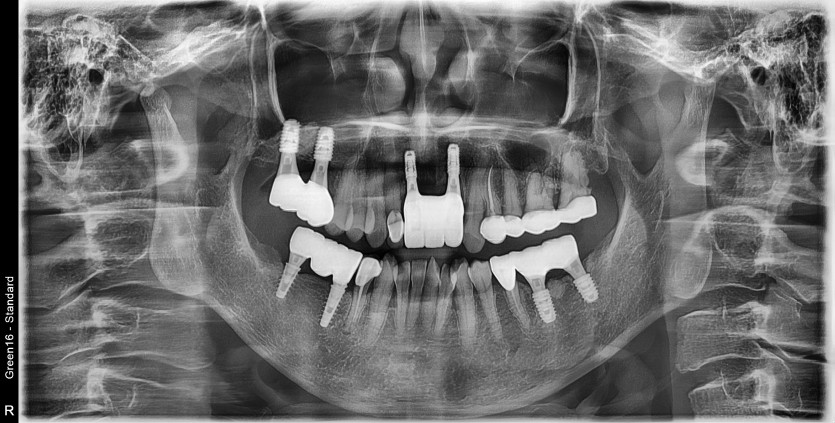

#11.22 타원 임플란트 제거 후

임플란트 재 수술 + 치조골 이식술 시행하였습니다.